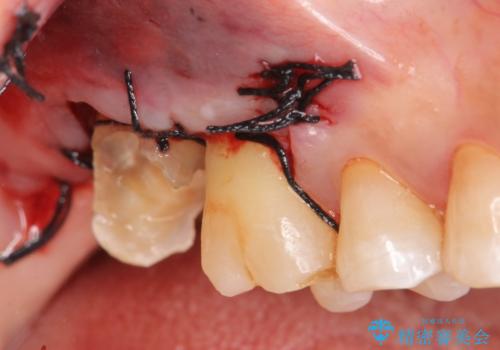

歯髄方向 歯肉方向へと深い 2種類の大きな虫歯

#17は失活歯で歯肉方向への縁下カリエス、#16は生活歯であるものの歯髄ギリギリの処置となるであろうとが予想される治療です。

歯周外科、マイクロスコープを用いた虫歯治療を行い歯を残す治療計画を立てます。

深い虫歯には歯周外科、マイクロスコープを用いた丁寧な虫歯の除去を行うことで歯の神経や歯そのものを残すことが可能になります。